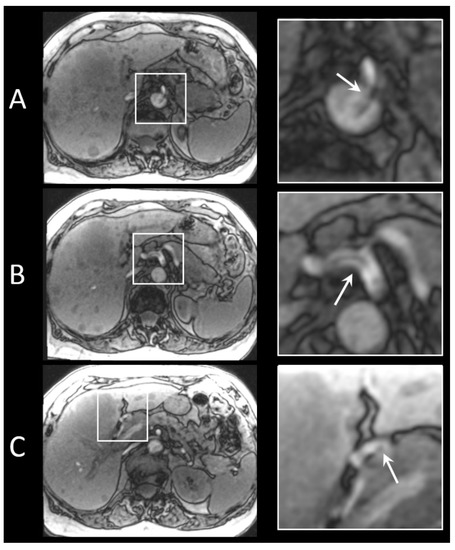

Based on these results, catheter A was selected as the guiding catheter during the clinical study. In Figure 5, an example of imaging acquired for localization of the catheters is shown. Catheter A exiting the aorta and entering the common hepatic artery is clearly recognisable; however, the small artefact at the tip of the microcatheter is difficult to detect.

Figure 5.

FLASH images of the two different catheters inserted in a patient treated with holmium SIRT for intrahepatic cholangiocarcinoma. (A) Catheter A exiting the aorta, entering the celiac trunk. (B) Catheter A entering the common hepatic artery. (C) Platinum/iridium marker at the tip of the microcatheter, positioned in the right hepatic artery.